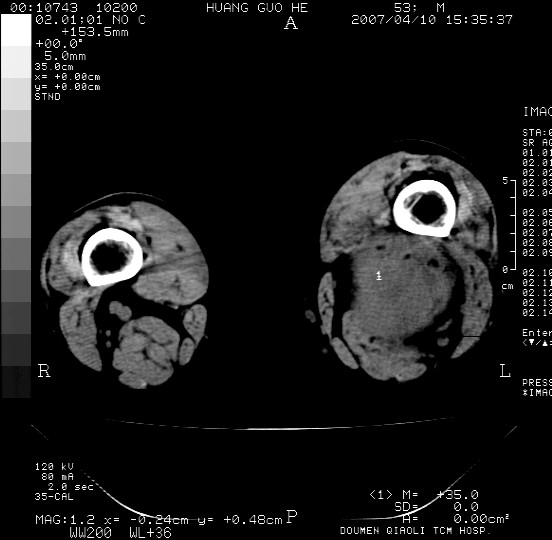

男性,左腘窝包块五个月,逐渐增大,疼痛功能受限,无发热。

查:远端血供差,质地硬。

左侧膝关节后国窝处略低密度软组织肿块,边界清楚,内见脂肪密度及高密度影.多考虑:软组织肿瘤_首选:脂肪纤维瘤.

左侧腘窝软组织肿块,边缘清晰,其内密度不均,周围骨组织无破坏,病灶增长较快,考虑:恶性病变(腘窝滑膜肉瘤可能),建议穿刺活检。